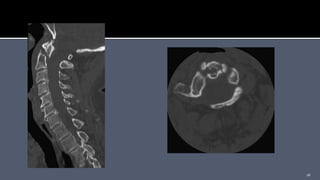

 Axial, sagittal, and coronal thin-cut (1-mm) reconstruction

images.

 Accurate detail of the bony anatomy.

 Position of the foramen transversarium through which the

vertebral artery runs.

 Measurement of the length of the screws

 Axial, sagittal,and coronal thin-cut (1-mm) reconstruction images.  Accurate detail of the bony anatomy.  Position of the foramen transversarium through which the vertebral artery runs.  Measurement of the length of the screws 15